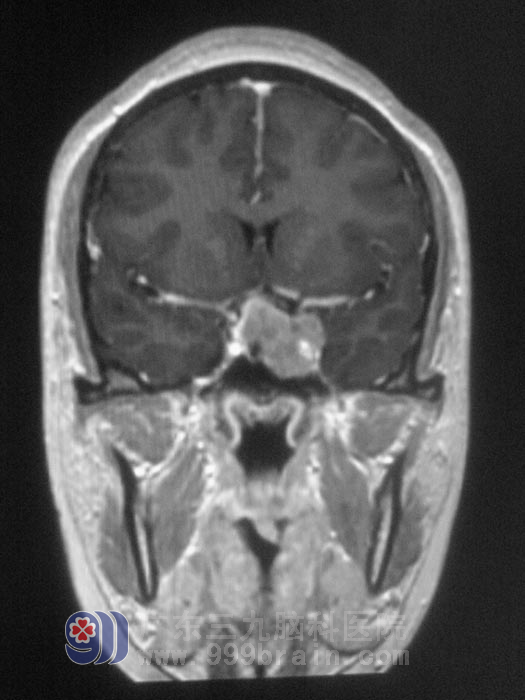

李小姐今年虽是25岁,却已是2个孩子的妈妈。但自从小孩断奶后,四年里仍然出现持续溢乳、闭经的情况,她刚开始以为是女性妇科问题,又听人说是因为月子没坐好,生完孩子卵巢早衰?李小姐非常担心,自己才25岁啊,怎么会卵巢早衰呢?一直在当地妇幼保健医院就诊。四年过去了,吃过无数的药,也做过多项检查,症状依然没有改善。大概在2个多月前无明显诱因出现头晕头痛,于是行头颅MRI检查,结果提示鞍区占位性病变,考虑垂体腺瘤可能。http://www.999brain.com/

术前

经人介绍,李小姐来到广东三九脑科医院垂体瘤诊疗中心,术前泌乳素171微摩尔每升,MR提示肿瘤大小为2.0*2.0*3.0cm,经讨论决定行经鼻蝶入路微创手术。11月22日,经德国进口导航仪定位,由垂体瘤诊疗中心鲁明主任主刀,在显微镜下见肿瘤呈淡红色胶状,予肿瘤切除,术后未出现脑脊液漏、视力视野损害及尿崩等并发症,复查泌乳素下降为37.6微摩尔每升。病理结果为:多激素分泌型垂体腺瘤。李小姐这颗悬着的心总算放下来了,恢复了以前的快乐生活。李小姐说广东三九脑科医院为她找到了起病原因,并治好了她,以后她自己也会注意,定期复查,保持良好心态。http://www.999brain.com/